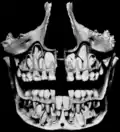

Formação dos dentes.- Angulo da mandíbula.

Dentes decíduos, erupção dos permanentes.

Dentes, e seio maxilar.